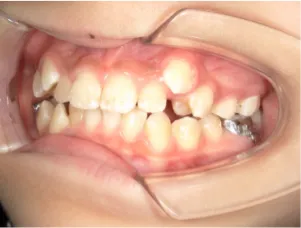

治療前①小5:生え変わり後期のため顔の成長を促進させる目的で拡大装置(アーチ形態の修正)と上顎前歯をそろえることを先行し、できるだけ非抜歯治療で進める予定を提案しました

| カウンセリング・診断結果 | 治療方法は精密検査、分析をして検討することをご理解いただき、矯正治療で抜歯をするかしないかの違いについて説明し治療を希望されたので精密検査を行いました。 精検の結果、顔立ちは下顎が後退したタイプの出っ歯(下顎後退型上顎前突)でV-shaped arch(歯列が狭い)、凸凹、八重歯になっていて、機能的にはべろのポジションが悪い低位舌があります。 口元は問題ありません。 |

| 行ったご提案・診断内容 | 生え変わりが終わってなくマルチブラケット法による咬合治療には早い時期のため、顔立ちの成長を促す目的で歯列弓(アーチ)の拡大と前歯を並べながら永久歯が生えるのを待ち、咬合治療開始時に再診断で抜歯、非抜歯を最終検討する提案をしました。 再診断時(写真②)、歯列の拡大と上顎前歯の並べ替えはされていましたが八重歯となったため抜歯、非抜歯を検討しました。 口元は特に問題がなく非抜歯で八重歯を改善するためのスペースを作ることが可能なため非抜歯治療を提案しました。 治療は、 ・拡大および上顎左右6を遠心移動させてスペースを作る 予定装置 |